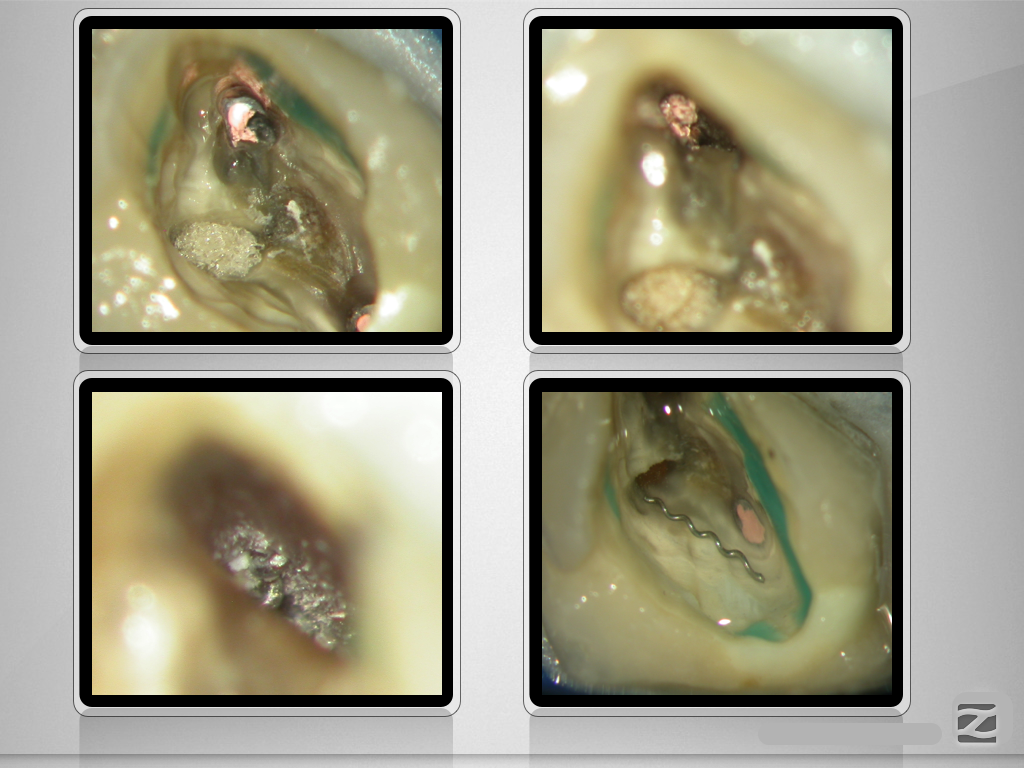

„Navigierte“ Fragmententfernung